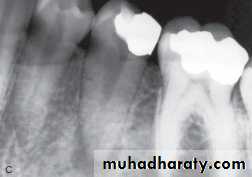

Tracing the sinus tract will provide objectivity in diagnosing the location of the problematic tooth. To trace the sinus tract, a size #25 or #30 gutta-percha cone is threaded into the opening of the sinus tract

UNIVERSITY OF MOSUL